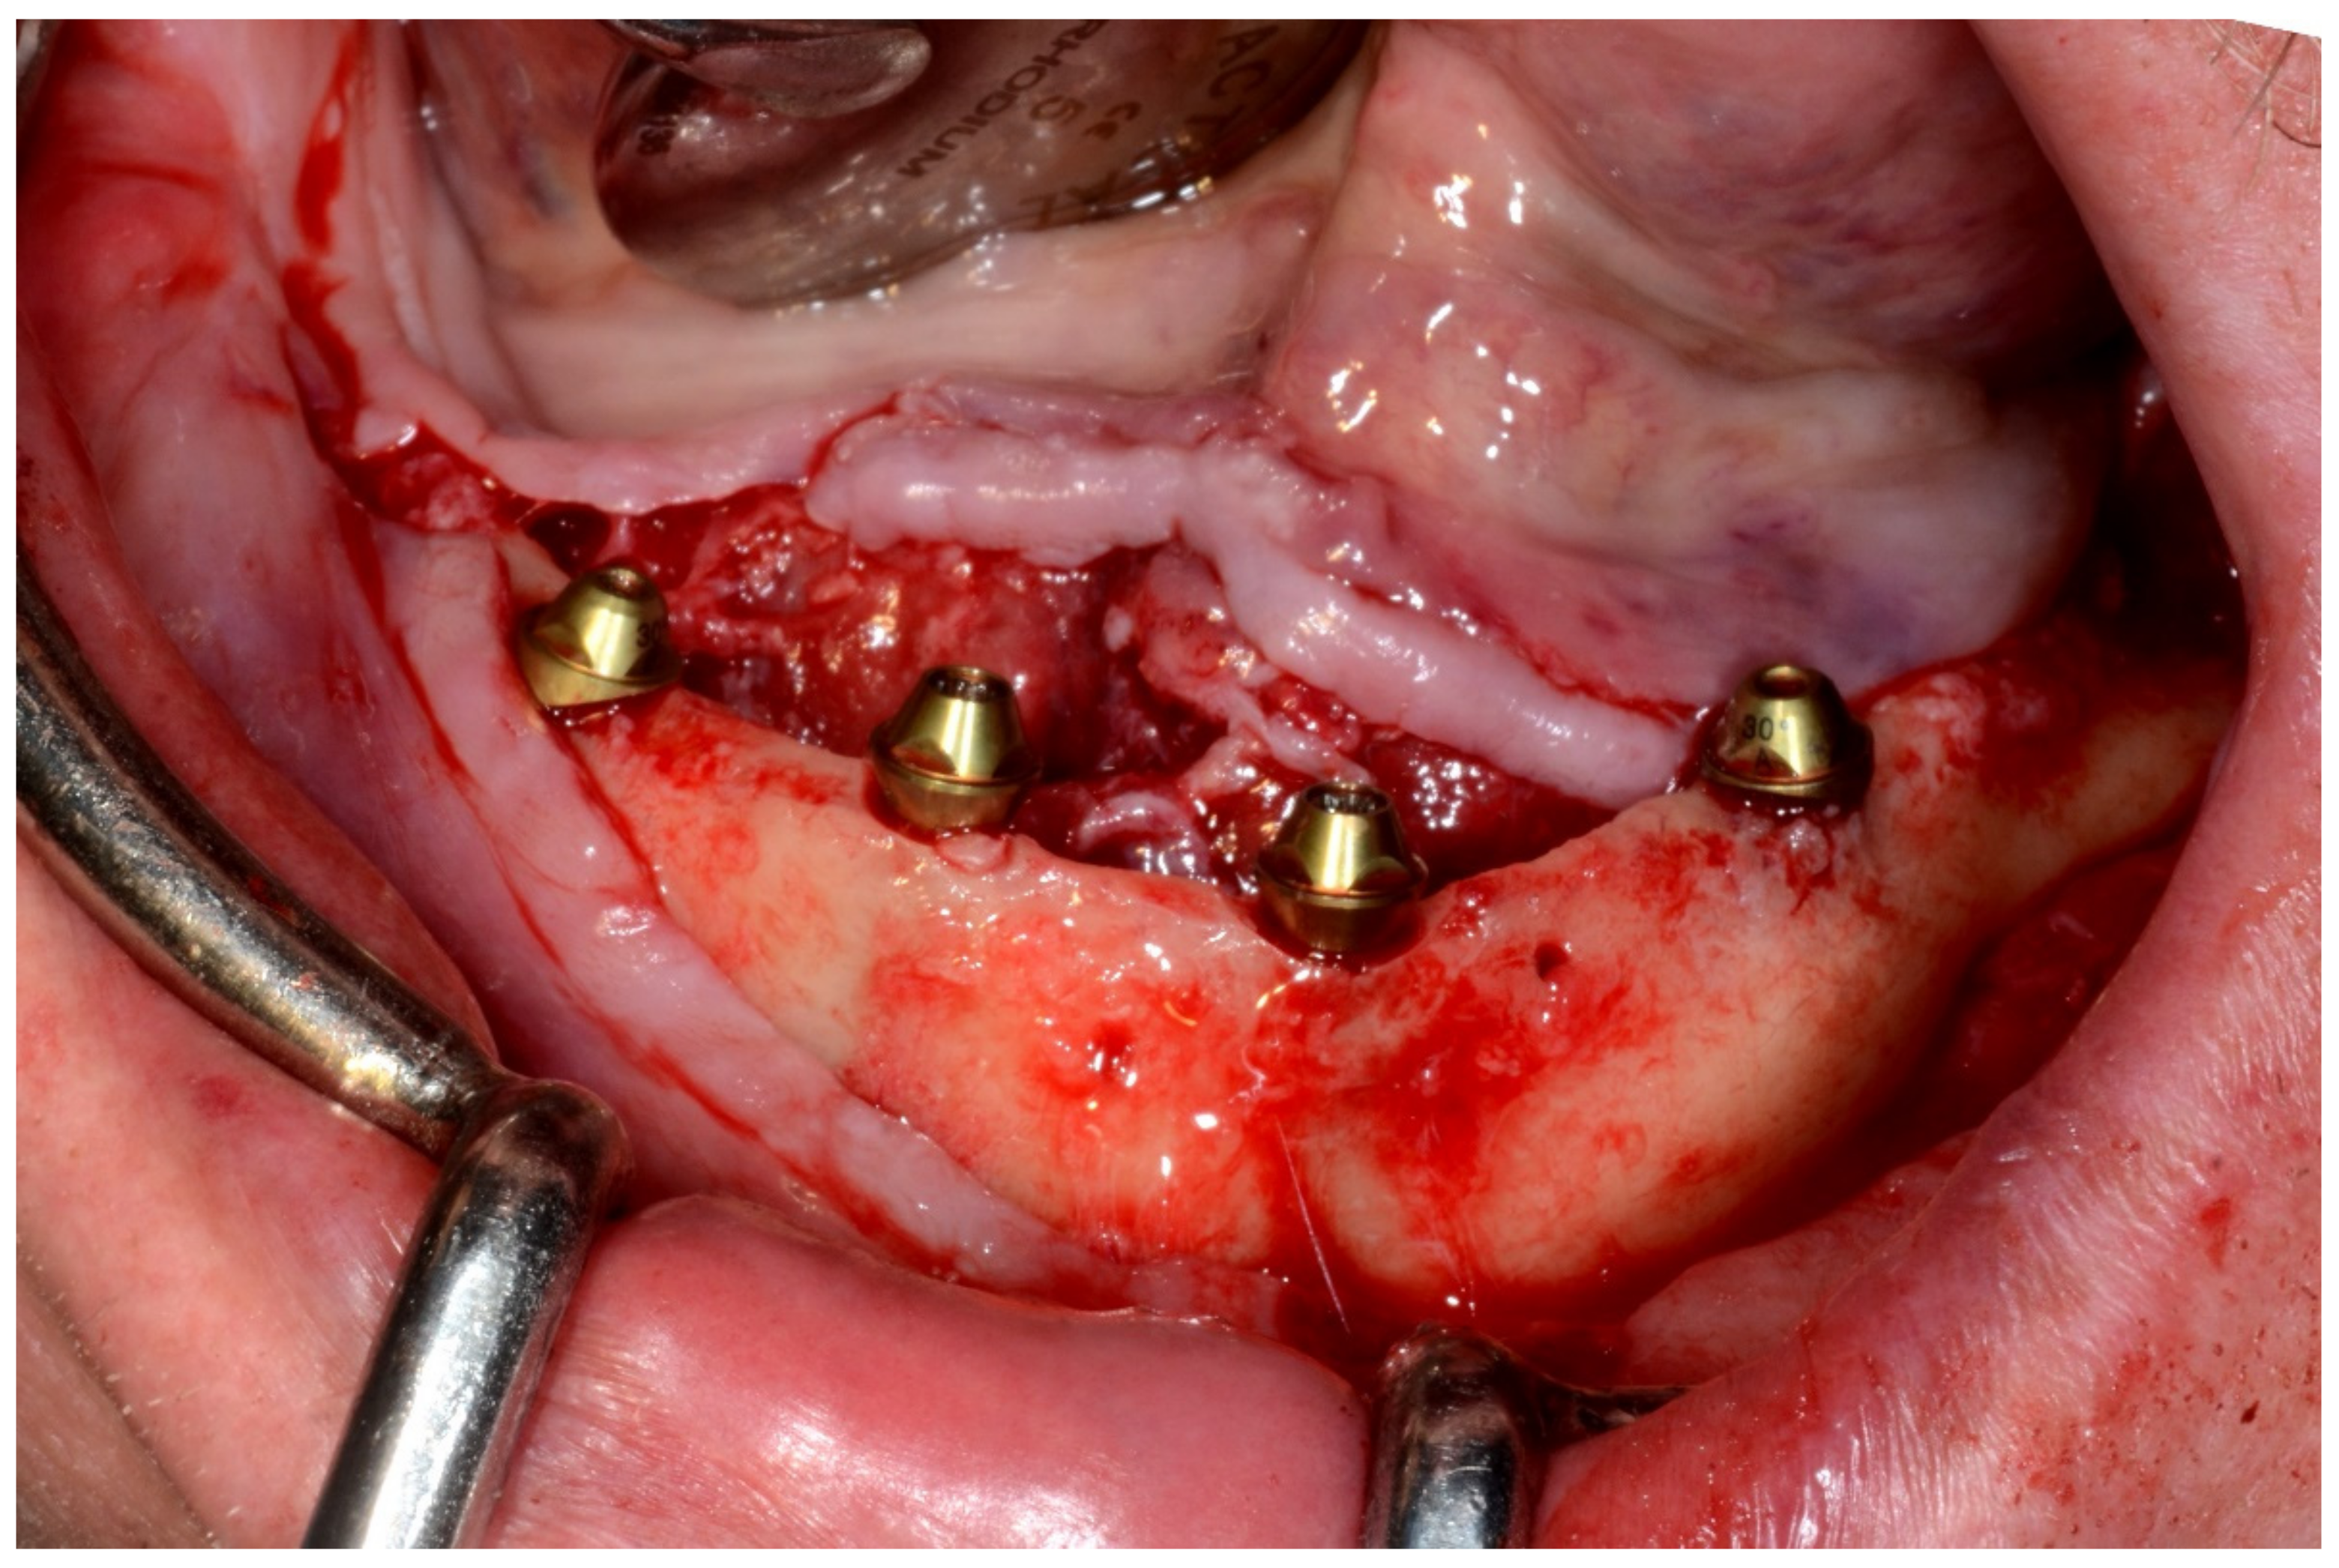

6.3.4. Intra-Operative Documentation:

In August 2019, four guided dental implants were placed at sites # 34, # 31, # 41, and # 44 (Figure 35 and Figure 36).

Figure 36.

Mandibular implants in place.